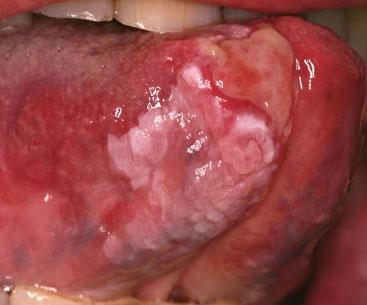

SQUAMOUS CELL CARCINOMA TONGUE

In 2007, cancer of the tongue was twice as common in men as in women. Smoking or the chewing of tobacco (including paan and gutka) are strongly implicated with its development. Alcohol consumption is also an aetiological factor, particularly of distilled spirits such as whisky, vodka or rum. Human papillomavirus, which may be transmitted via oral sex, has been detected in pre-malignant as well as malignant lesions. Leukoplakia, which is usually encountered after the age of 40 years, is a pre-malignant lesion presents as a white patch and so any isolated white area that cannot be diagnosed on visual inspection should be referred to an oral surgeon.